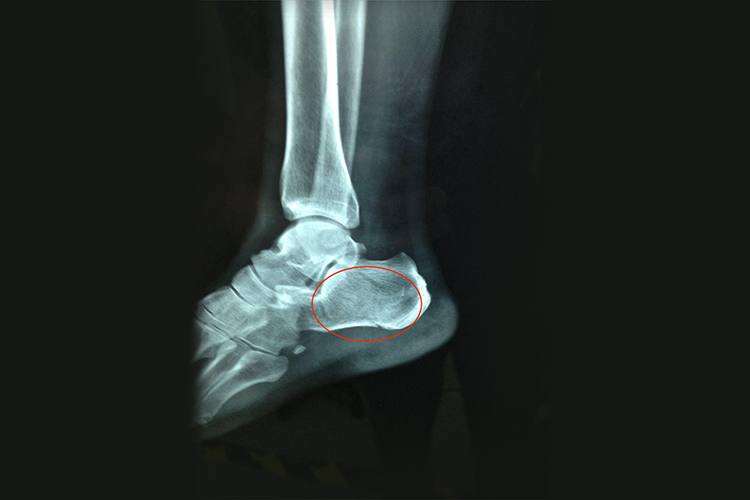

骨裂的恢复时间因多种因素而异,一般来说需要6-12周,甚至需要更长的时间。

- 像胫骨、腓骨等部位的骨裂,由于血运相对较差,恢复时间会稍长,大概6-8周初步愈合,12-16周能恢复正常活动。

骨裂恢复期间要注意休息,避免过早活动导致骨裂加重。保持均衡的饮食,摄入足够的营养,尤其是富含钙、蛋白质和维生素D的食物。按照医生的建议进行康复训练,逐渐增加活动量。定期复查X线检查,了解骨裂愈合情况。注意固定部位的皮肤护理,防止压疮。患者在恢复过程中要保持耐心,遵循医生的指导,进行合理的治疗和康复。